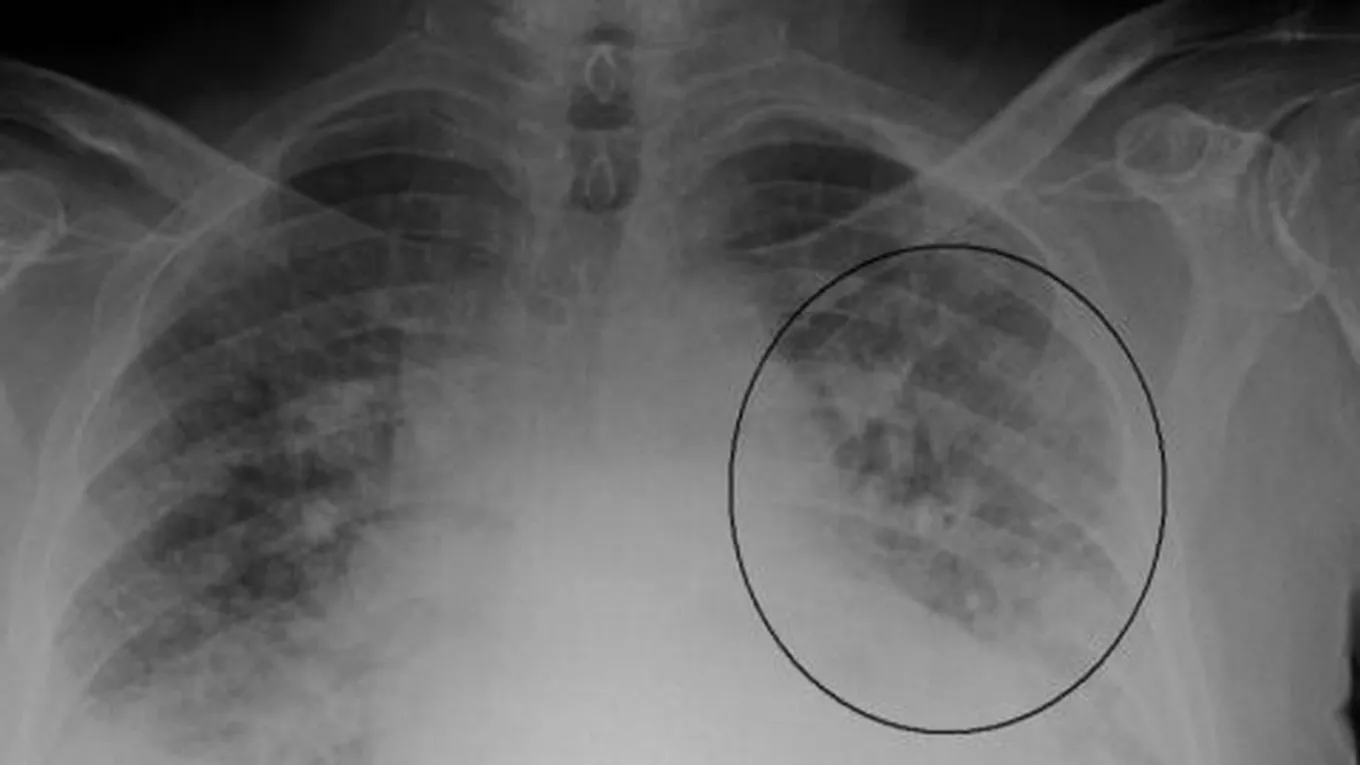

تحدث الإصابة بماء الرئة أو ما يُعرَف بالوذمة الرئويّة (بالإنجليزية: Pulmonary edema) نتيجة زيادة الضغط في الأوعية الدمويّة في الرئة ممّا يؤدي إلى تراكم السوائل في الرئة وصعوبة عمليّة التنفّس، ويُعدّ العلاج بالأكسجين الخطّ العلاجيّ الأول لضمان حصول الشخص المصاب على كميّات كافية من الأكسجين، ولإيصال الأكسجين للشخص المصاب يمكن استخدام قناع الوجه، أو إدخال أنبوب بلاستيكيّ خاص إلى داخل الأنف، أو قد يتمّ اللجوء إلى استخدام جهاز التنفّس الاصطناعيّ (بالإنجليزية: Mechanical ventilator)، ويساعد حصول الشخص المصاب على الأكسجين على التخفيف من أعراض الوذمة.[1][2]